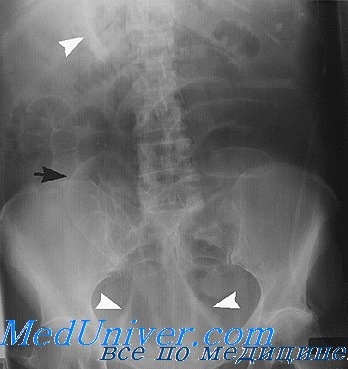

Современные технологии в медицине: рентгенодиагностика заболеваний желудка